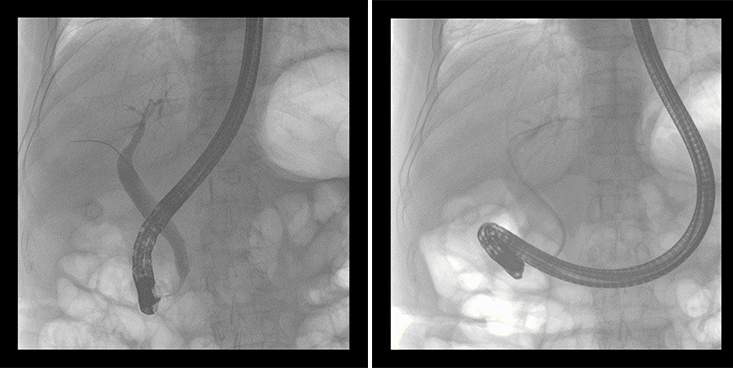

普愛醫(yī)療移動式平板中C為本次ERCP手術提供實時無損高清影像,幫助醫(yī)生精準定位。“成像效果非常棒!完全不輸國際大牌的醫(yī)學影像設備……”鼓樓醫(yī)院江北國際醫(yī)院內鏡中心手術團隊對普愛醫(yī)療移動式平板中C的成像效果給與了高度的評價。

移動式平板中C術中影像

在消化內科主任的領導和多科室全力配合下,南京鼓樓醫(yī)院江北國際醫(yī)院成功完成了首例ERCP手術。